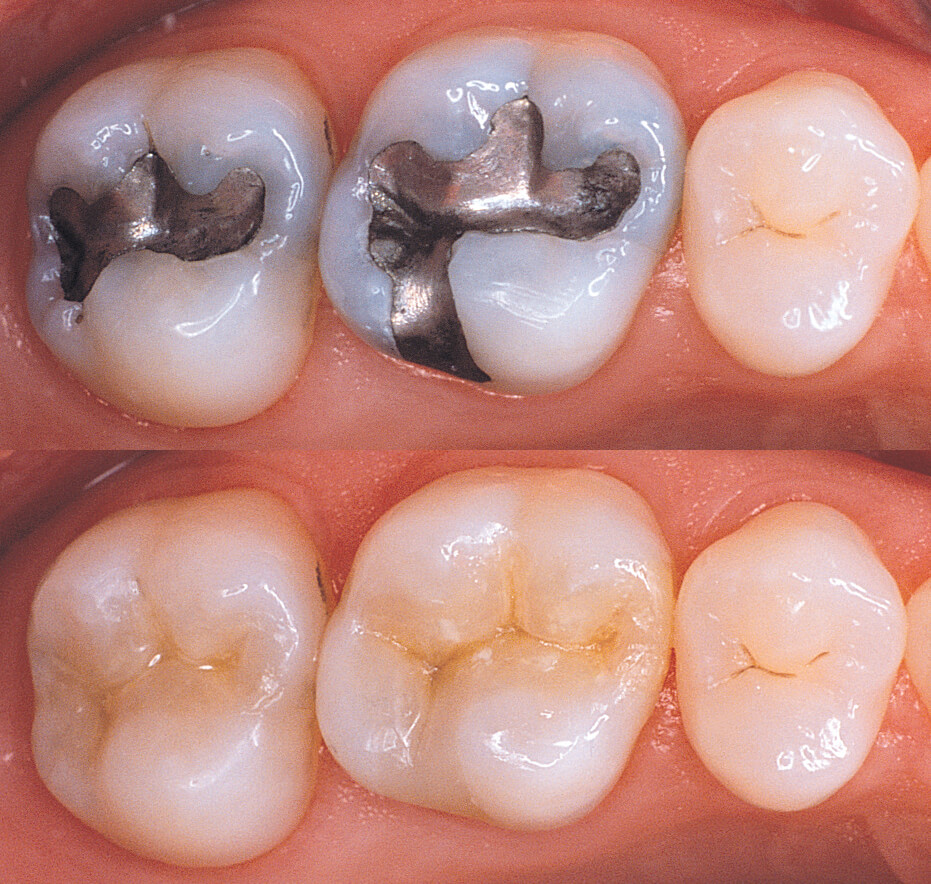

Odontologie restauratrice S3

4 examensExamens disponibles

QCU Odont restau S3 #1

QCU Odont restau S3 #2

QCU Odont restau S3 #3

QCU Odont Restau S3 #4

Odontologie Conservatrice complexe

3 examensExamens disponibles

CC oc complexe

OC qcm

QCM OC S6